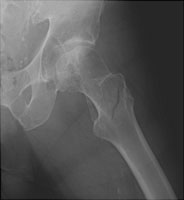

Intertrochanteric Fracture

Extra capsular fractures which involve the femoral trochanters include intertrochanteric and subtrochanteric fractures. The intertrochanteric fracture is by far the most common and is classified according to the status of the lesser and greater trochanter. If neither of these is fractured, the fracture is termed a two part fracture. If either the lesser or greater is fractured, then the fracture consists of three parts. If both are fractured, the fracture is termed a four part fracture. These fractures generally result from a fall and typically occur in postmenopausal women.

- Click on the image for a larger versionAAP radiograph of the left hip. This demonstrates an intertrochanteric fracture of the left femur.